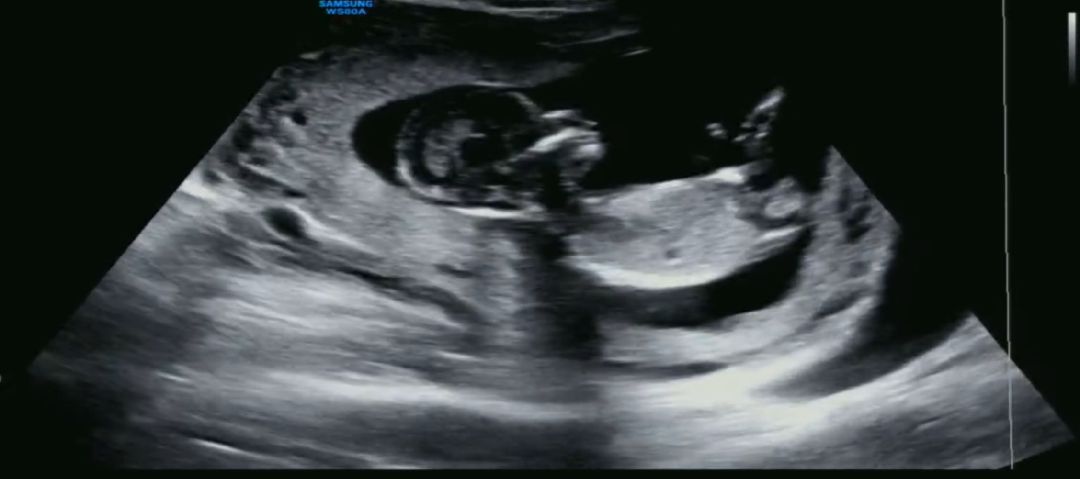

각도법 고수님 13주차 사진 봐주세요❤️❤️

각도법 어떻게 보는지 모르는데 ㅠ 이 사진으로도 확인이 가능할까요??? 남편이 너무너무 궁금해해요 ㅎㅎ

아기 척추뼈가 잘 안 보이는 사진이지만 아들에 한표 드립니다.